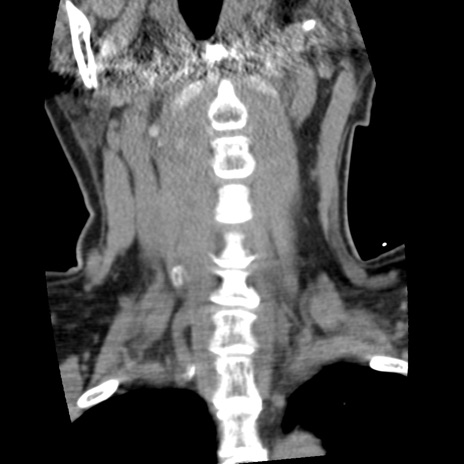

症例50 頚椎CT(冠状断像)

頚椎CT